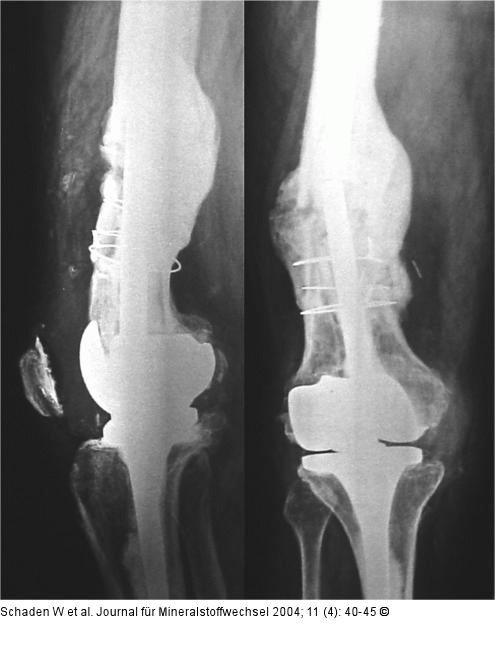

Abbildung 3: Kniegelenksprothese - ESWT Ausheilungsergebnis 6 Monate nach ESWT in geringer Varusfehlstellung. |

Ausheilungsergebnis 6 Monate nach ESWT in geringer Varusfehlstellung. |